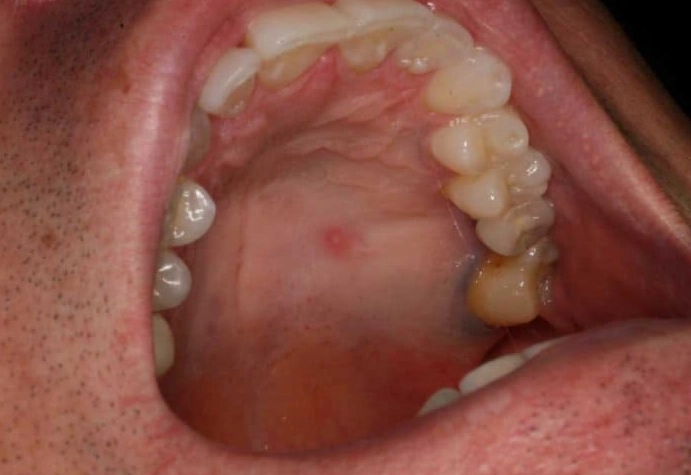

- Palatal Torus / Mandibular Torus: This was my personal mystery lump. A torus is a slow-growing, bony protrusion. A palatal torus is a hard, bony lump in the middle of the roof of the mouth. A mandibular torus is on the inside of the lower jaw, near the premolars. They feel like solid rock—because they are bone. They're genetic, harmless, and only need removal if they interfere with dentures.

If it's a single, hard, bony-feeling lump right in the midline, it is overwhelmingly likely to be a palatal torus, which is benign bone growth. Cancer on the hard palate is relatively rare and usually has other features (ulceration, redness, growth). Still, a dentist needs to confirm it.